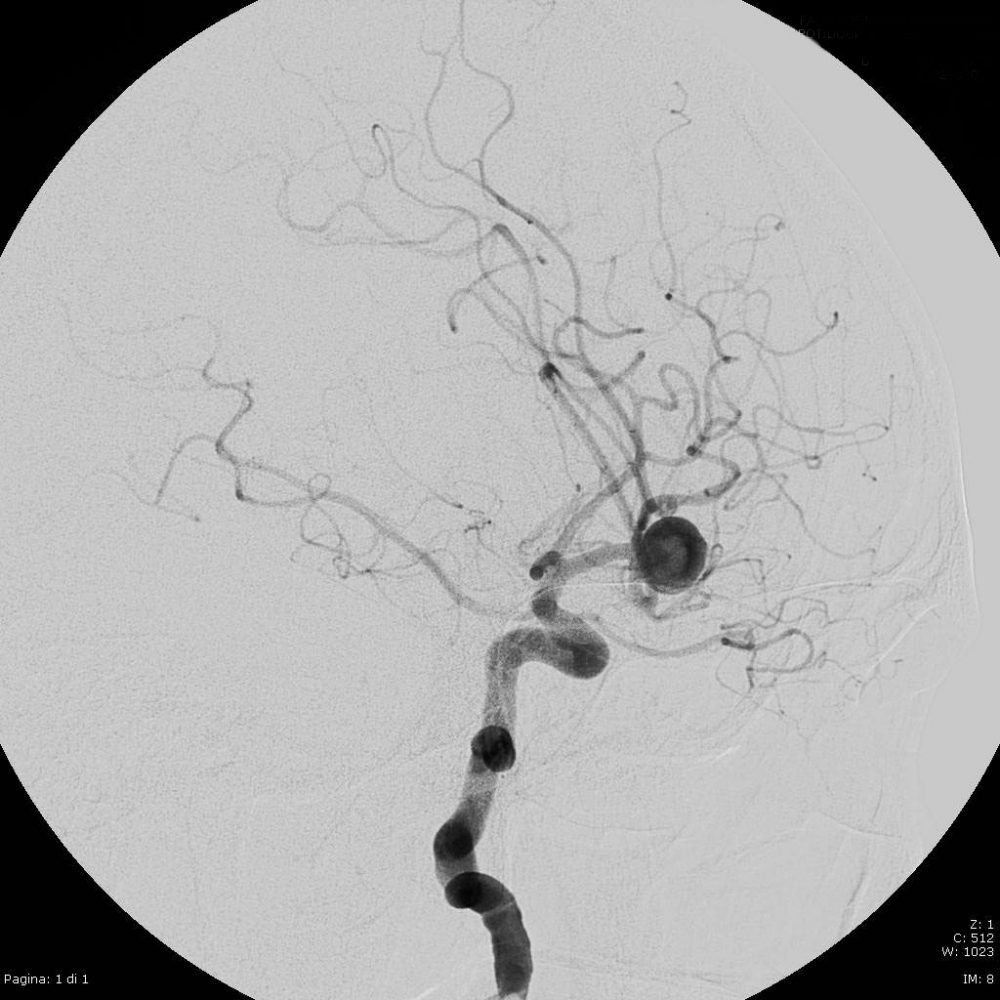

Aneurisma cerebrale angiografia pre operatoria Dott Andrea Barbanera

Doppio aneurisma cerebrale intervento per via endovas

Cause. Sintomi. Diagnosi. Trattamento. Un aneurisma è un rigonfiamento (dilatazione) della parete di un'arteria. Gli aneurismi che si verificano nelle arterie del cervello (arterie cerebrali) vengono detti aneurismi cerebrali. Si può verificare in qualsiasi arteria.. Introduzione. Cause. Sintomi. Quando chiamare il medico. Pericoli. Diagnosi. Cura e terapia. Prevenzione. Fonti e bibliografia. Introduzione. Con il termine aneurisma si indica la dilatazione di un vaso sanguigno a causa della debolezza della parete, in genere nei punti dove il vaso si ramifica.